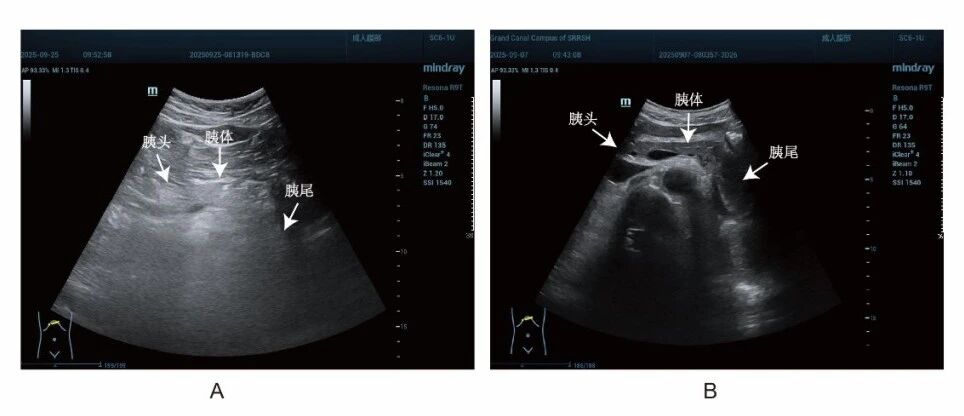

(白色箭头所指分别为“胰头”“胰体”“胰尾”,A:因胃肠道气体干扰,胰尾显示不清,B:胰腺各部分显示清晰)